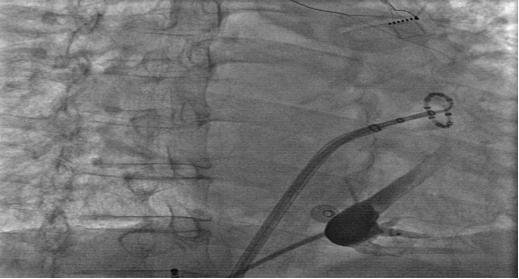

冠状静脉造影后,找到Marshall静脉

进行Marshall韧带消融后,基质标测提示左房嵴部和部分二尖瓣峡部区域电位消失

经过充分的术前准备,南大二附院心内科心律失常团队通力合作,先后为两位持续性房颤患者成功实施了该项手术,Marshall静脉细小,解剖位置变异较大,容易漏掉,因此需首先定位该静脉。通过冠状静脉造影寻找Marshall静脉,之后送入导丝及球囊。两例房颤患者术中Marshall静脉化学消融后,对于导管消融难以实现透壁损伤的左肺静脉和左心耳交界嵴部区域电位消失,左肺静脉隔离很快完成,同时仅仅消融几个点就彻底阻断了二尖瓣峡部,患者最终成功恢复了窦性心律。